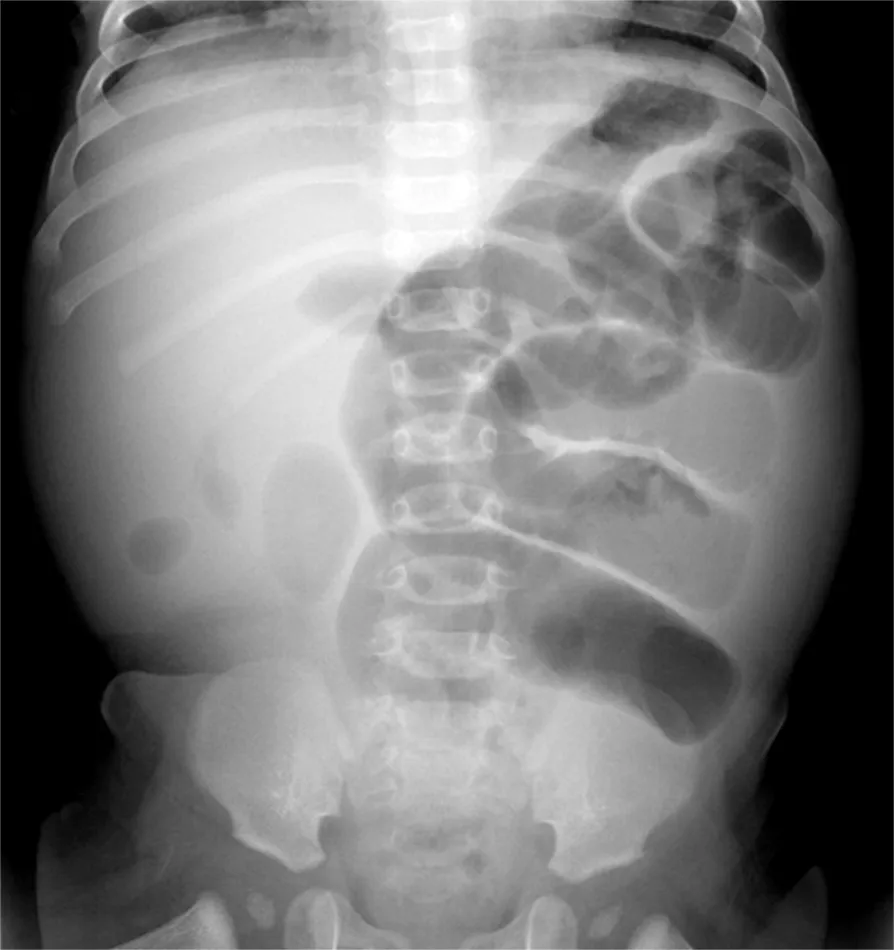

폐색의 정확한 원인과 위치를 알아내기 위해서는 복부 CT 검사가 필수적입니다. 또한, 장의 위치와 그 기능적 상태를 더 자세히 알아보기 위해 조영제를 사용하여 소장의 엑스레이 촬영을 시간대별로 수행하기도 합니다.